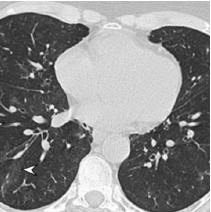

Chest

| Respiratory symptoms | |

| R04.2 | Hemoptysis |

| R06.00 | Dyspnea |

| R06.02 | Shortness of breath |

| R05.9 | Cough |